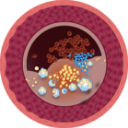

PRIJE TERAPIJE

Na slici lijevo vidimo suženje desne koronarne arterije kod 66-godišnjeg muškarca, dijagnosticirano pomoću invazivne koronarografije. Vidljivo je značajno suženje u proksimalnom segmentu uzrokovano kalcificiranim aterosklerotskim plakom, koji blokira protok krvi.